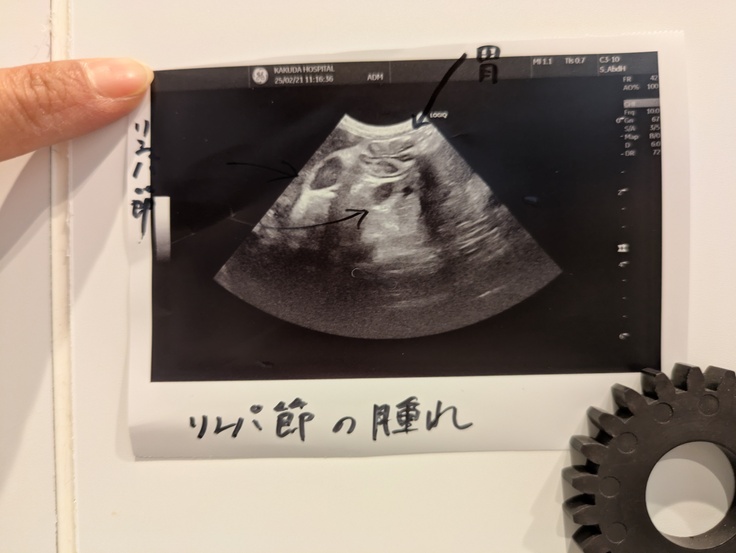

私は喉や腸になにかがあるんじゃないかと疑っていましたがエコーの結果リンパ節が腫れていることが分かりました。

飲み薬は吐いてしまうので抗生剤の注射となりました。

また、血液検査では炎症は口腔内にあることが分かりやはり抜歯とかスケーリングだね。というお話になりました。

また吐き気が気になっていましたので吐き気止めと点滴をしていただきました。